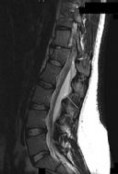

Figures 1 through 3 show sagittal and axial MRIs and a radiograph from a

77-year-old woman with leg pain when standing and walking of 1 year duration. The pain improves when she leans forward. She has been in physical therapy, taken oral analgesics, and had epidural injections with minimal relief. What is the best next step?

4. Microdiskectomy Discussion: B

The patient has lumbar stenosis of L2-3 and L3-4. She has no spondylolisthesis or instability. For her condition, spinal fusion plays a minimal role. She has no evidence of instability, and her condition can be addressed through laminectomy only. No role exists for microdiskectomy, because her disease results from a combination of ligamentum flavum hypertrophy and facet hypertrophy.